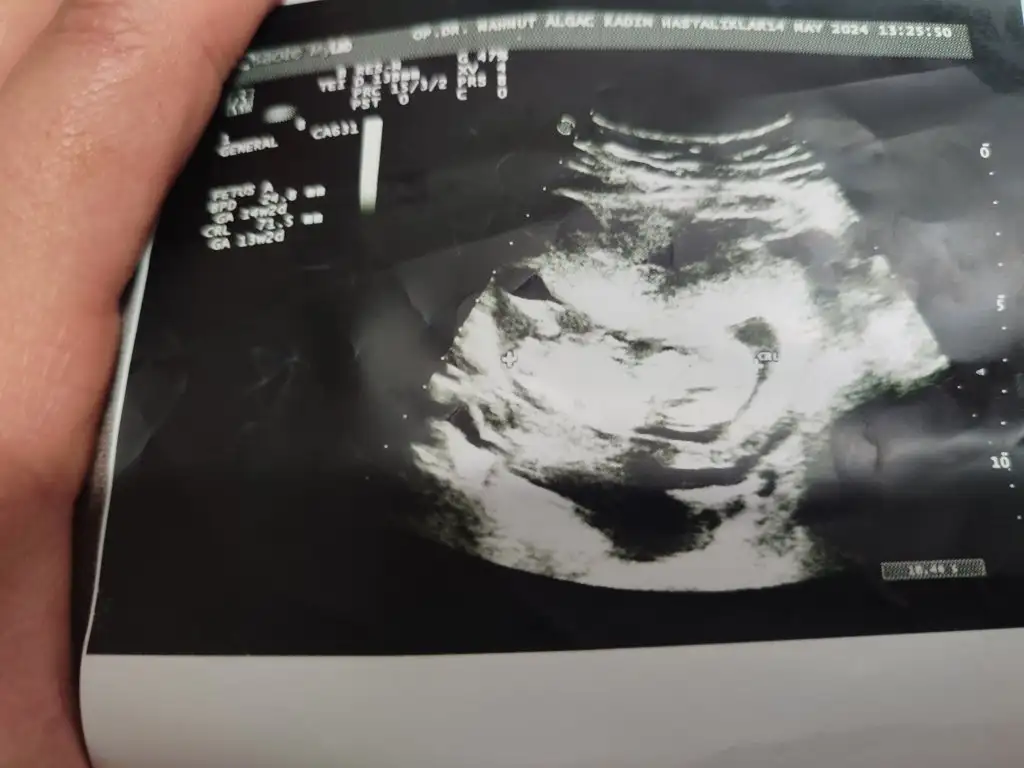

12+6 ydı bir hafta geç döllenme aslında 13+5 olması lazımdı 😂 karından ultrason